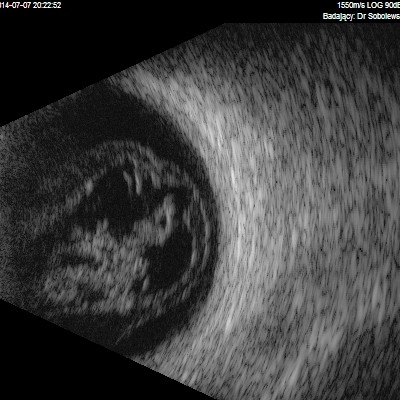

Przedstawiane obrazy ultrasonograficzne® są oryginalne i pochodzą z mojej praktyki lekarskiej